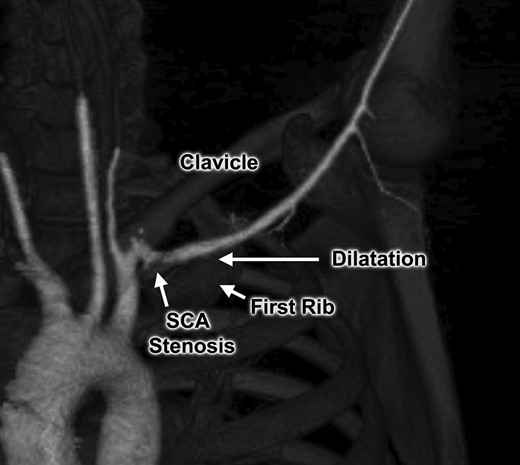

An otherwise healthy 44-year-old female nurse presented with a painful left arm and hand, 2 weeks after she had fallen onto the outstretched left arm while hiking. She sought medical attention when she developed Raynaud’s phenomenon and was unable to feel pulses at the wrist, and clinical evaluation suggested thrombosis of the left brachial, radial and ulnar arteries. Contrast-enhanced computed tomography (Figs 1 and 2) and catheter-based arteriography (Fig. 3) confirmed the diagnosis and showed that while there was no cervical rib or other bony abnormality, there was focal stenosis of the left subclavian artery at the level of the first rib with mild post-stenotic dilatation. These findings indicated that the subclavian artery was the source of thromboembolism and the patient was successfully treated with catheter-based thrombolysis to resolve the acute obstruction. She was discharged on a direct oral anticoagulant but returned within several weeks after recurrence of symptoms. She was found to have rethrombosis and again underwent thrombolysis, followed by anticoagulation with an alternative agent, and was then referred to our specialized TOS center for surgical treatment.

Computed tomography angiogram with 3D reconstruction, demonstrating focal left subclavian artery (SCA) stenosis and post-stenotic dilatation within the thoracic outlet.